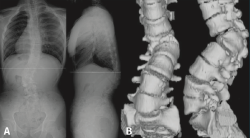

Figura 5. Espondiloartropatía degenerativa.

Otros hallazgos radiológicos frecuentes, como las anomalías congénitas de transición lumbosacra, espondilolistesis, secuelas de epifisitis, la espina bífida oculta, las escoliosis leves o moderadas, la hiperlordosis, espondiloartropatía, etc., se encuentran casi por igual en pacientes con y sin dolor lumbar (Figuras 5, 6 y 7)(22,23).

Figura 6. Secuelas de epifisitis. Reproducido de Perolat et al.(22).

Por otro lado, alteraciones degenerativas denominadas como “enfermedades” que forman parte de síndromes radiculares asociadas con dolor lumbar se observan con frecuencia en asintomáticos.